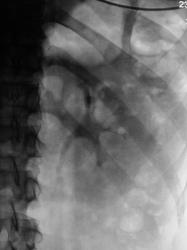

Мы решили сразу после исследования сделать томографию мочевого пузыря.

А если, по большому счету и объективно, то линейная томография весьма рано, некоторыми специалистами, "сдана в архив".